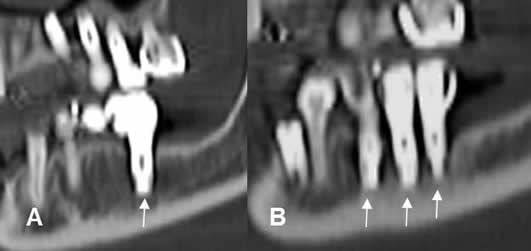

Después de colocado el implante, la oseointegración requiere de al menos 3 meses en la mandíbula y 6 meses en el maxilar. (12). (Fig 32).

Aunque su valoración es principalmente clínica, la radiología puede aportar información adicional. La radiolucencia alrededor del-implante y la pérdida de altura del hueso, de más de un tercio de la longitud del implante o más de 2 mm en cinco años se han postulado como signos de fracaso del implante. (8). (Fig 33 A, B y C).

Fig 32. Seguimiento de implantes.

A y B: TAC reconstrucción sagital. Implantes mandibulares, con adecuada óseo-integración.

Fig 33 A. Complicacion de implante.

A: TAC axial, B: TAC reconstrucción panorámicay C: TAC reconstrucción transversal. Implante con extremo, que rompe el borde inferior del seno maxilar.

Fig 33 B. Cuerpo extraño.

A: TAC axial, B: TAC reconstrucción sagital y C: TAC reconstrucción coronal. Tornillo de un implante suelto, dentro del seno maxilar.

Fig 33 C. Infección del implante.

A: TAC axial, B: TAC reconstrucción coronal y C: TAC reconstrucción sagital. Infección del implante, el cual se ha caído. Hay gran lesión lítica que destruye el maxilar, por osteomielitis.